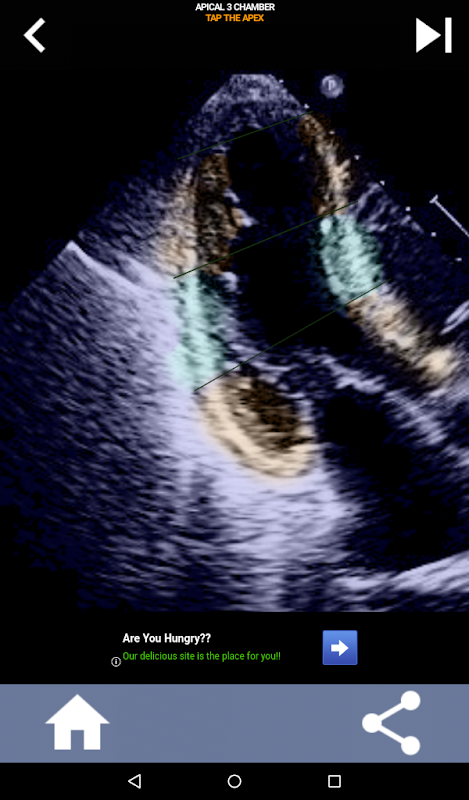

Pendekatan visual berbasis kuis untuk mempelajari segmen jantung AHA: Ekokardiografi

Aplikasi ini akan menguji pengetahuan Anda menggunakan gambar gema yang sebenarnya, yang sering saya temukan sebagai metode pengajaran terbaik.